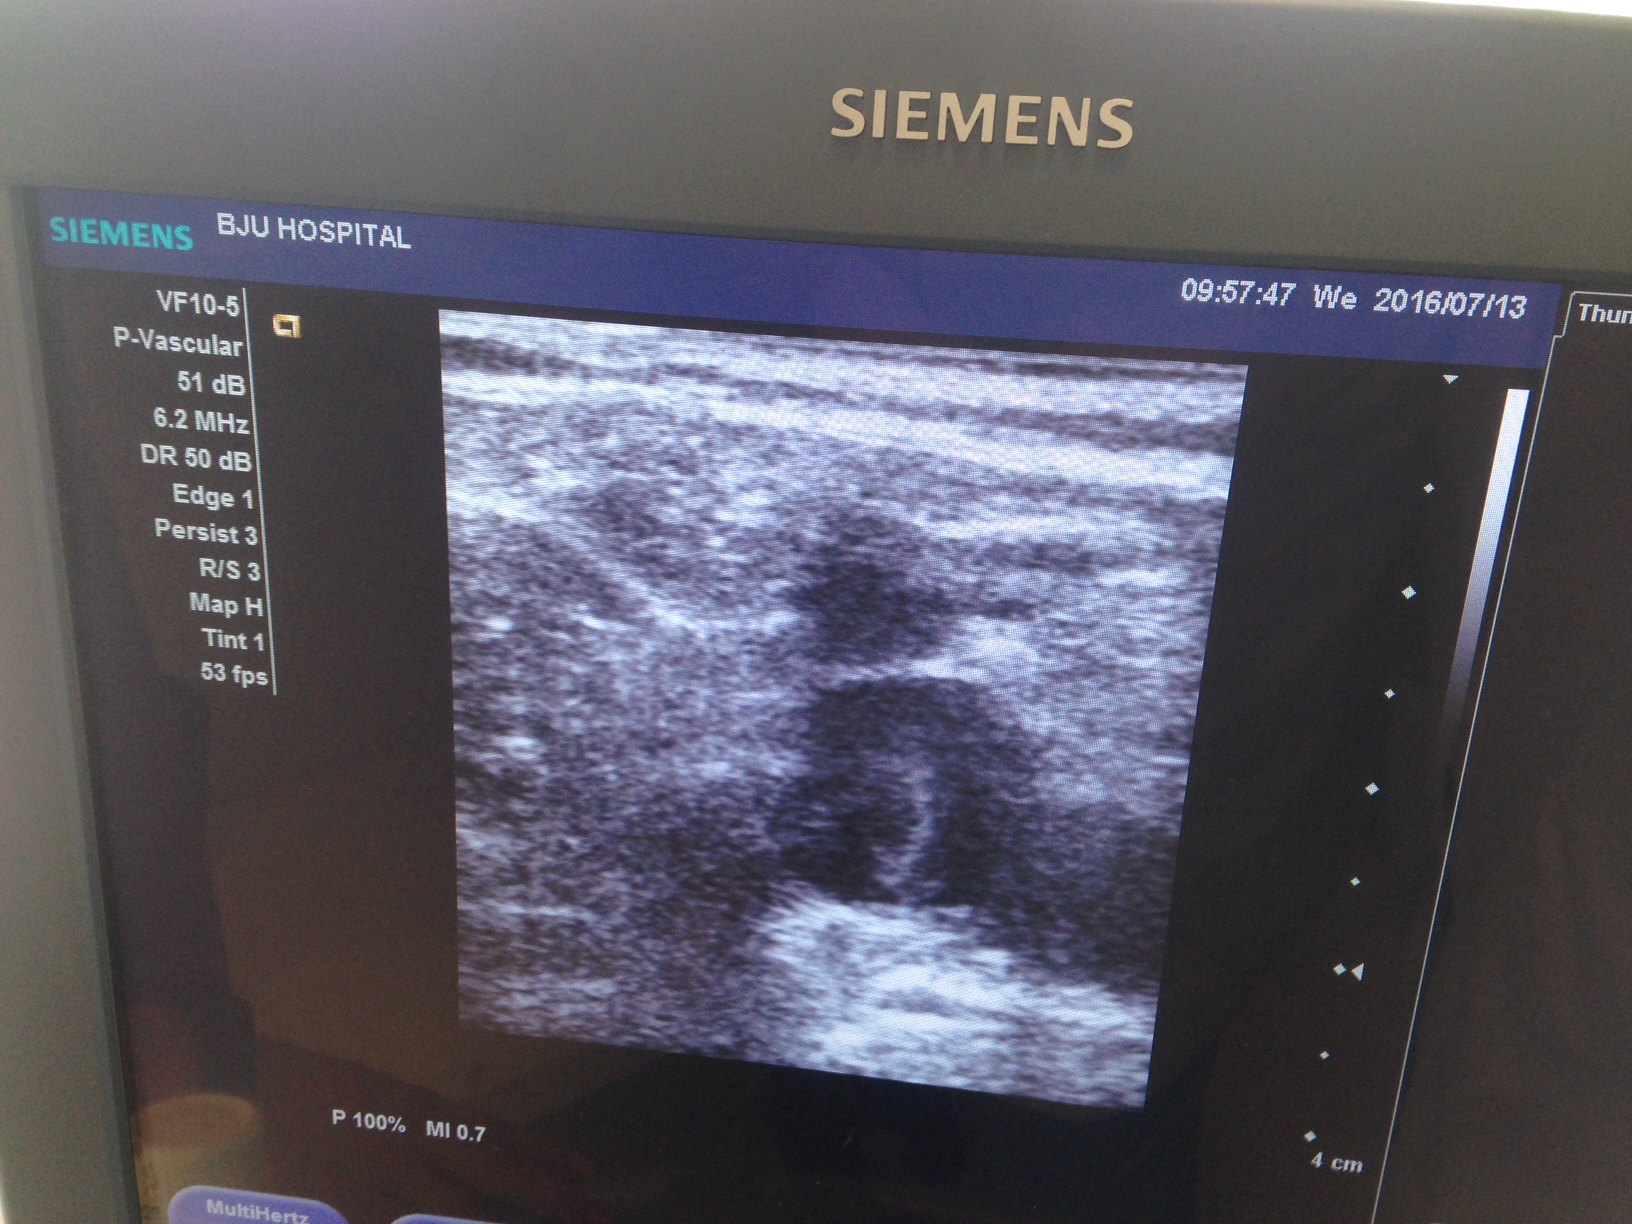

-多普勒超声在下肢血管疾病的诊断中具有重要的作用。它可以查看深浅静脉有否狭窄和反流,动脉供血有否不足等。

-当站立位时,表浅静脉主干处于充盈状态,可以测量大隐静脉,小隐静脉的直径,检测有否反流,及反流的时间。对于病理性交通静脉,站立位多普勒血管超声的辨识度要高于平卧位。

1. 术前由手术医生亲自进行多普勒超声检查。让患者站立位,手术医生要测量大、小隐静脉与深静脉汇合处,及中段和远段的管径,并检测有否血液的反流及反流时间。以此来评估大小隐静脉有否功能不全。